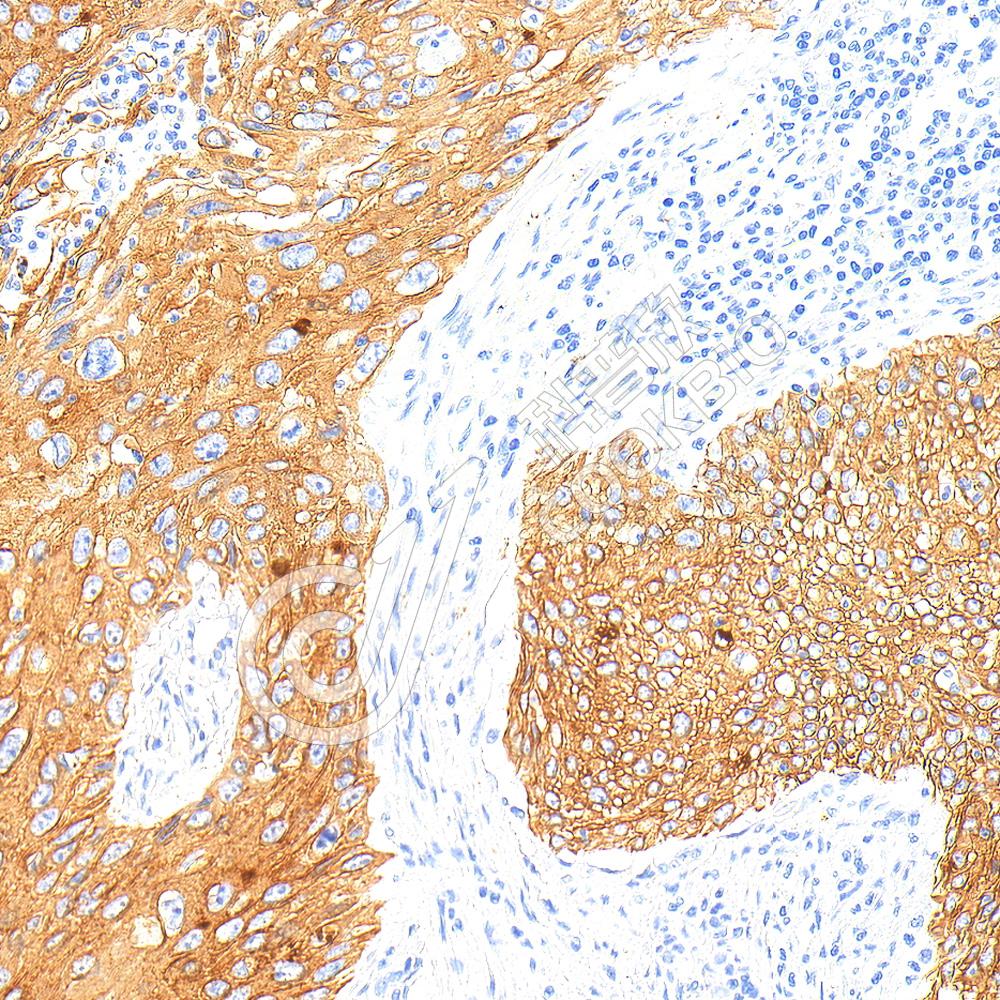

IHC检测Phospho-Tau(S202/T205)蛋白(货号 K5450180).

样品: 小鼠阿尔茨海默氏症脑模型, 4%多聚甲醛 (货号KSG1101) 固定12-24小时.

抗原修复: 柠檬酸抗原修复液(干粉, pH 6.0) (KSG1201), 高压锅均匀喷气计时2分钟.

—抗: 1: 300稀释, 4℃ 孵育过夜.

二抗: S-vision免疫组化多聚二抗(山羊抗兔),即用型 (货号KB3906), 室温孵育20分钟.